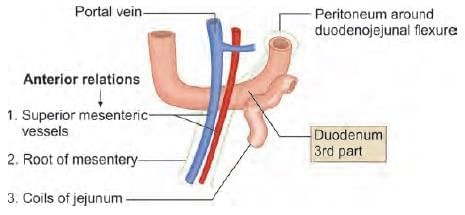

Anterior relations of third part of duodenum are all, except: (INI-CET May 2023)